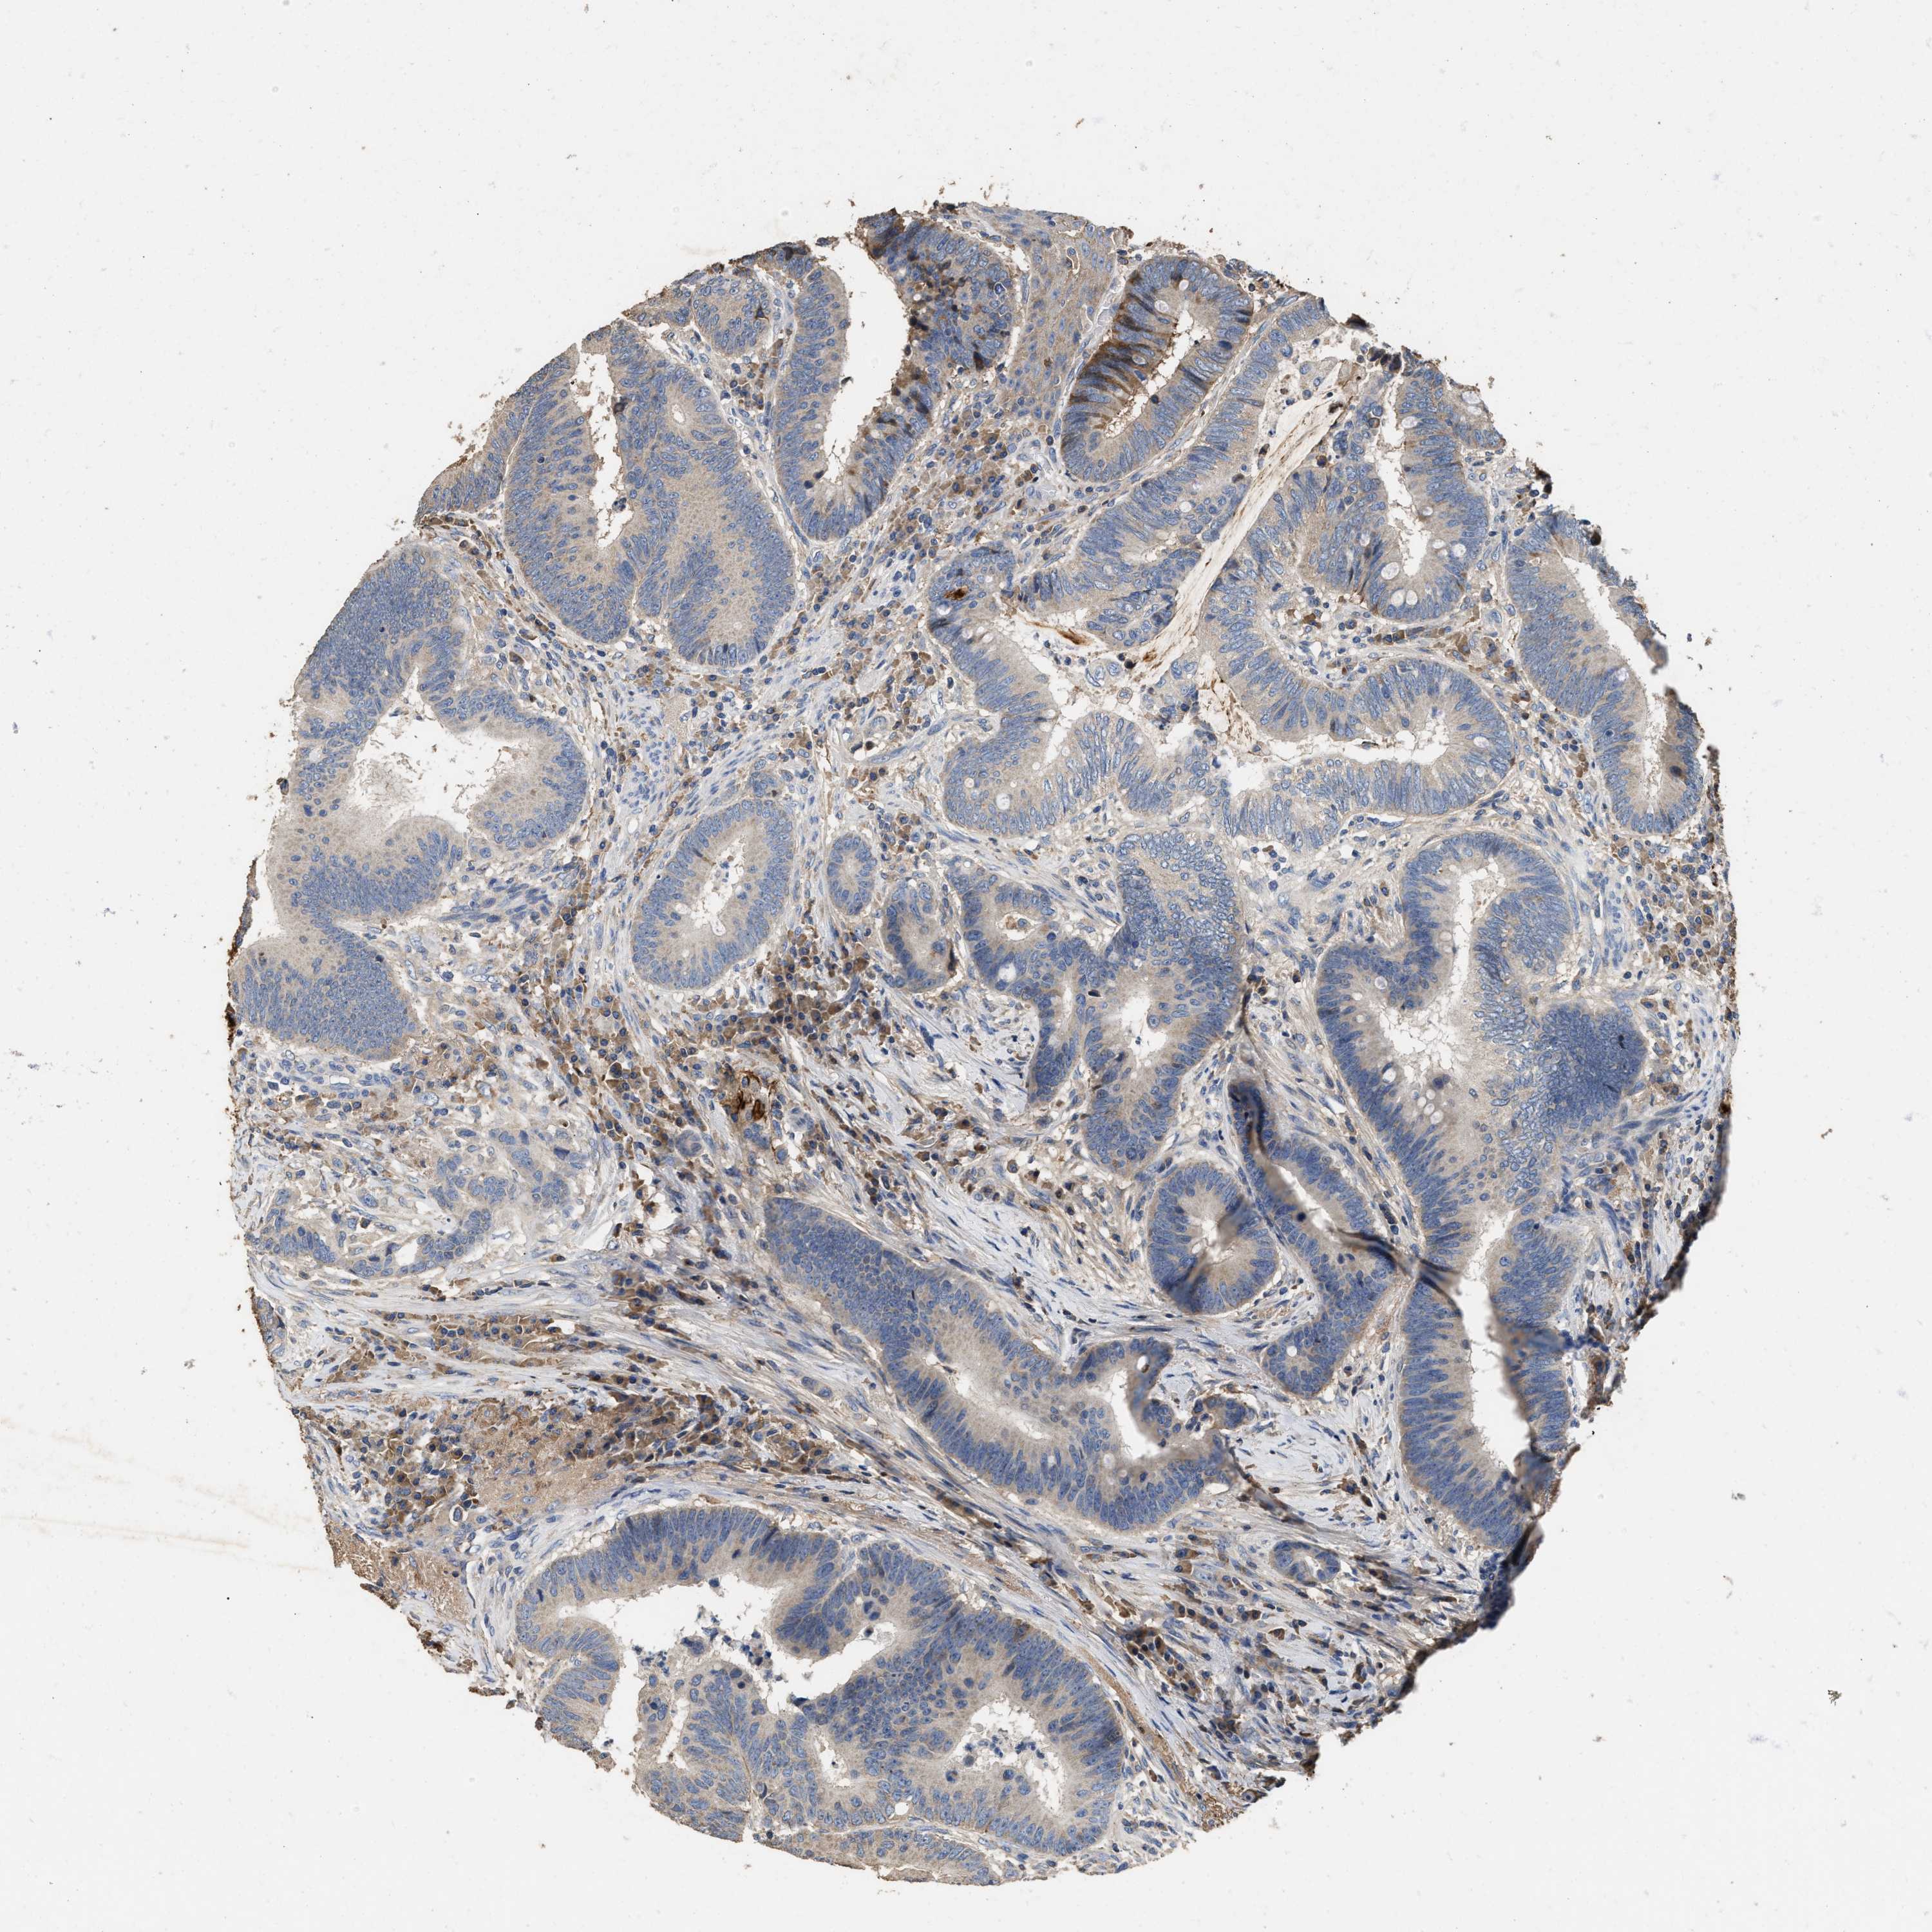

CANCER COLORECTAL CANCER Show tissue menu

Colorectal cancer

Human cancer

Colon adenocarcinoma